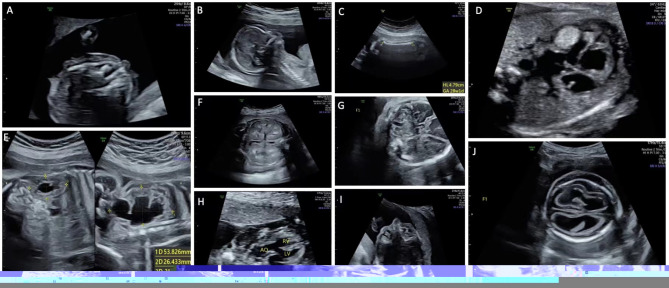

Abstract Image